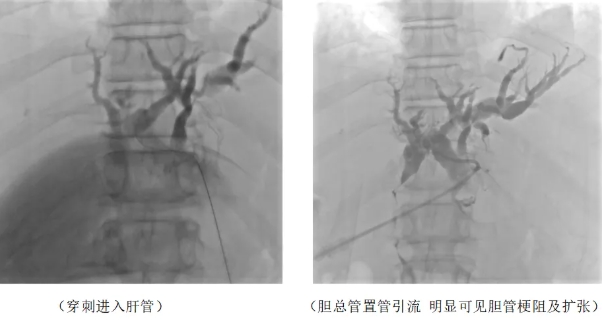

第一期手术,专家团队采用经皮肝穿刺胆管引流术(PTCD),先为患者引流减压。手术开始,在DSA的精准引导下,成功穿刺扩张的肝内胆管。这一步骤必须精准无误,稍有偏差就可能损伤周围重要组织。成功穿刺后,团队熟练地置入引流管,这根引流管就像为堵塞的河道开辟的新泄洪通道。随着手术完成,淤积的胆汁顺着引流管顺利引出体外。神奇的是,术后仅 24 小时,患者的黄疸症状便开始缓解,原本蜡黄的皮肤渐渐恢复色泽,肝功能指标也开始趋于稳定,这为后续治疗赢得了宝贵时间。

PTCD 手术即经皮肝穿刺胆管引流术,是在影像设备引导下,经皮肤穿刺进入扩张的肝内胆管,建立体外胆汁引流通道的技术。它就像给 “水漫金山”的胆道系统安装了一个“临时排水泵”。适用于各种原因引起的胆道梗阻,尤其是无法手术切除的恶性肿瘤导致的梗阻性黄疸。

通过及时引出淤积胆汁,能快速降低胆红素水平,缓解黄疸症状,减轻肝脏负担,改善患者全身状况,为后续治疗创造条件。